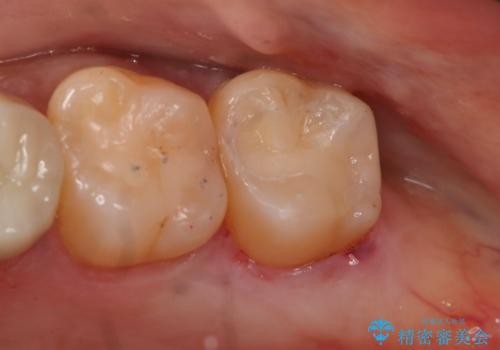

- 左上奥歯の銀歯のやり変えを希望された患者様です。

白くしたいとの事だったので形態・切削量を考慮し、セラミックインレーでの治療を計画しました。

保険材料と比較し、セラミックは劣化しない材料なので二次的な虫歯を防ぐことが出来ます。